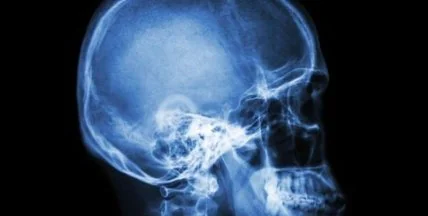

Черепно-мозговые травмы обычно приводят к массовой гибели клеток в отдельных областях мозга. Результатом этих изменений может стать ухудшение работы сознания и нарушение некоторых физических функций, вплоть до потери речи, парализации конечностей, а также ухудшения долгосрочной и краткосрочной памяти.

Массовая гибель клеток мозга в результате черепно-мозговой травмы связана с тем, что внутри него начинает накапливаться жидкость и развивается отек. Сейчас единственный эффективным (и крайне рискованным) методом лечения отека является трепанация черепа.

В ходе нового исследования ученые нашли способ замедлить процесс развития отека с помощью наночастиц, покрытых антителами. Такие частицы позволят остановить миграцию моноцитов за счет отвлечения иммунной системы — при введении их в кровь иммунная система направляет основные силы на борьбы с ними, игнорируя мозг.